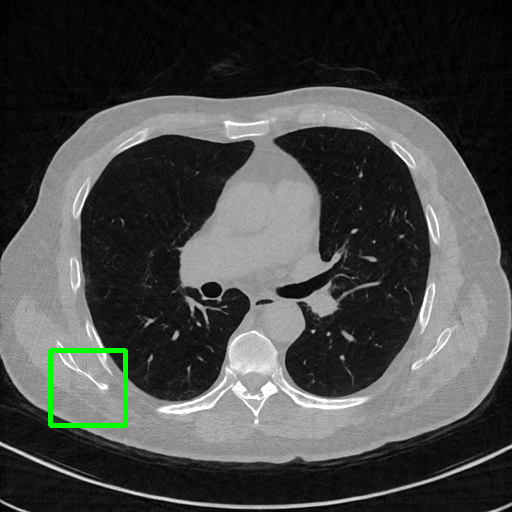

Qualitative comparison. We also visualize the reconstructed images of these methods in Fig. 4 with = [72, 96 ,144] (See more visualizations in Appendix). In all three rows, our DuDoTrans shows better detail recovery, and sparse-view artifacts are suppressed. Further, when decreasing , where raw sinograms are too messy to be restored and low-quality images from FBP are too hard to capture global features, Transformer-based models exhibit reduced performance. The phenomena suggests that we should design suitable structures with the Transformer and CNNs, facing with different cases.

Ground Truth

FBP

FBPConvNet

DuDoNet

ImgTrans

DuDoTrans